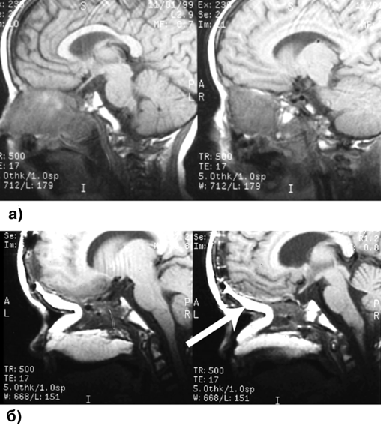

После удаления опухоли дефект ТМО закрывают лоскутом надкостницы или свободным лоскутом жировой клетчатки из передней брюшной стенки с фиксацией швами или фибрин-тромбиновым клеем. Этот лоскут дополняется вторым, надкостнично-фасциальным, лоскутом на ножке. При обширных дефектах применяются более сложные методы пластики (лоскутом большого сальника, кожно-мышечным лоскутом прямой мышцы живота, лоскутом большой грудной мышцы, кожно-мышечным лоскутом передней зубчатой мышцы и фрагментами ребер) (рис. 2). При необходимости последующего протезирования глазного яблока пластика дефекта мягких тканей осуществляется с учетом этого обстоятельства.

Рисунок 2. МРТ до (а) и после (б) операции больного с рабдомиосаркомой решетчатой пазухи, носоглотки, правой половины полости носа, правой гайморовой пазухи. Стрелкой показан трансплантат прямой мышцы живота